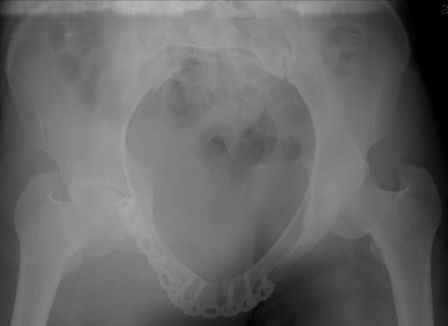

Серия до- и послеоперационных снимков этой пациентки. Хотя бы post factum обсудить. Не знаю, что можно сделать с задними отделами стержневым аппаратом, но три крепких парня открытым путем с помощью "волшебных" слов еле-еле смогли отрепонировать - сзади все было очень ригидно!

Здравствуйте, Евгений! У меня видна только дооперационная проекция inlet.

я бы остановился на передней раме, операция - 30 мин, в таком варианте вроде бы репозиция - ничего, но когда давать нагрузку, ведь в лонном сочленении тоже есть подвижность? а если не давать - зачем операция?